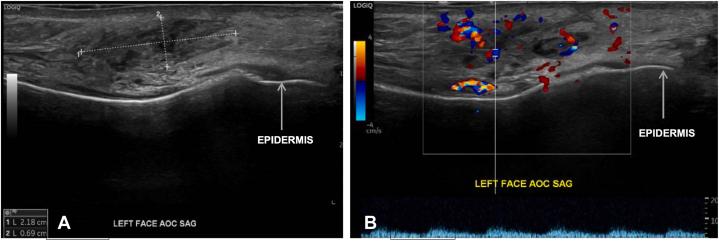

Recurrent Kimura disease in an African American woman with concordant ultrasound imaging: A case report and literature review.

JAAD Case Rep. 2025 Apr 26;62:31-34. doi: 10.1016/j.jdcr.2025.04.019. eCollection 2025 Aug.